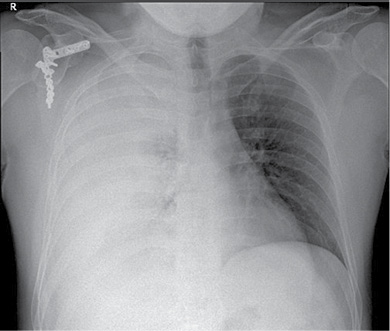

36 m. vyras P. D. atvyko į Gastroenterologijos skyrių patikslinti diagnozės planine kepenų biopsija. Praėjus 8 val. po procedūros, pacientas pajuto maudimą po dešiniuoju šonkaulių lanku punkcijos vietoje. Apžiūros metu pacientas buvo hemodinamiškai stabilus. Atlikus laboratorinius tyrimus, nustatyta saiki anemizacija (hemoglobinas – 128 g/l; norma – 135–160 g/l). Įtariant kraujavimą pilvaplėvėje, atlikta pilvo echoskopija: pilvo ertmėje laisvo skysčio nematyti, dešinėje pleuroje iki 4 cm laisvo skysčio ruožas. Konsultuota krūtinės chirurgo. Rekomenduota atlikti krūtinės ląstos rentgenogramą (Ro). Nustatytas beveik neoringas dešinysis plautis, pastebėta hidrotorakso požymių (1 pav.). Įtarus jatrogeninį hemotoraksą, krūtinės chirurgas atliko diagnostinę pleuros punkciją. Patvirtinus hemotorakso diagnozę, drenuota dešinė pleuros ertmė, išsiskyrė 400 ml kraujo. Tuo metu aktyvaus kraujavimo nenustatyta, hemodinamika išliko stabili, kartotiniuose laboratoriniuose tyrimuose – saiki anemizacija (hemoglobinas – 120 g/l). Atlikus kontrolinę rentgenogramą, nustatytas sumažėjęs skysčio kiekis pleuroje, buvo matyti kompresinių dešiniojo plaučio pakitimų. Įtariant sukrešėjusį hemotoraksą, atlikta skubi krūtinės ląstos KT (2 pav.), kuri patvirtino įtariamą patologiją. Tolesniam operaciniam gydymui pacientas perkeltas į Krūtinės chirurgijos skyrių. Atlikta skubi VATS (angl. video assisted thoracoscopic surgery). Operacijos metu pašalinta 1 000 ml krešulių, aktyvaus kraujavimo nenustatyta, diafragmos kupole rasta nedidelė hematoma. Pooperacinis periodas sklandus (3 pav.). Po trijų dienų geros būklės pacientas išleistas į namus.

3 pav. Krūtinės ląstos priekinė rentgenograma baigus gydymą